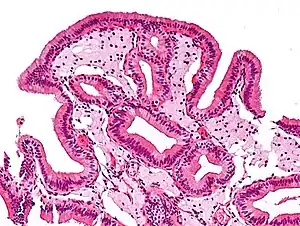

Micrograph of cholesterolosis of the gallbladder, with an annotated foam cell. H&E stain.

The name strawberry gallbladder comes from the typically stippled appearance of the mucosal surface on gross examination, which resembles a strawberry. Cholesterolosis results from abnormal deposits of cholesterol esters in macrophages within the lamina propria (foam cells) and in mucosal epithelium. The gallbladder may be affected in a patchy localized form or in a diffuse form. The diffuse form macroscopically appears as a bright red mucosa with yellow mottling (due to lipid), hence the term strawberry gallbladder. It is not tied to cholelithiasis (gallstones) or cholecystitis (inflammation of the gallbladder).[2]